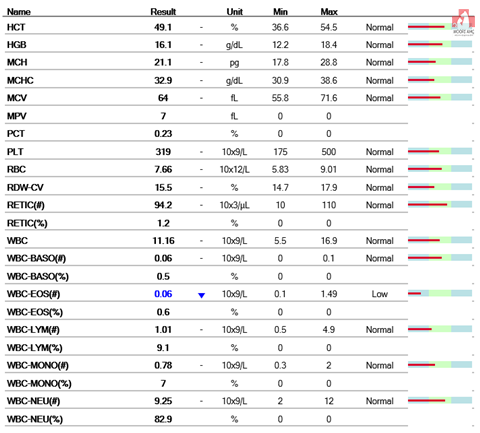

먼저 마취전 검사를 하기로 했어요.

다행히 혈액검사상으로는 탈장에 의한 근 손상으로 AST, CK가 올라간 것 이외의 특이 소견은 없었습니다.

그러나 혈액 검사 상 신장의 수치는 양호하고 마취에 관해서는 괜찮다고 생각됩니다.